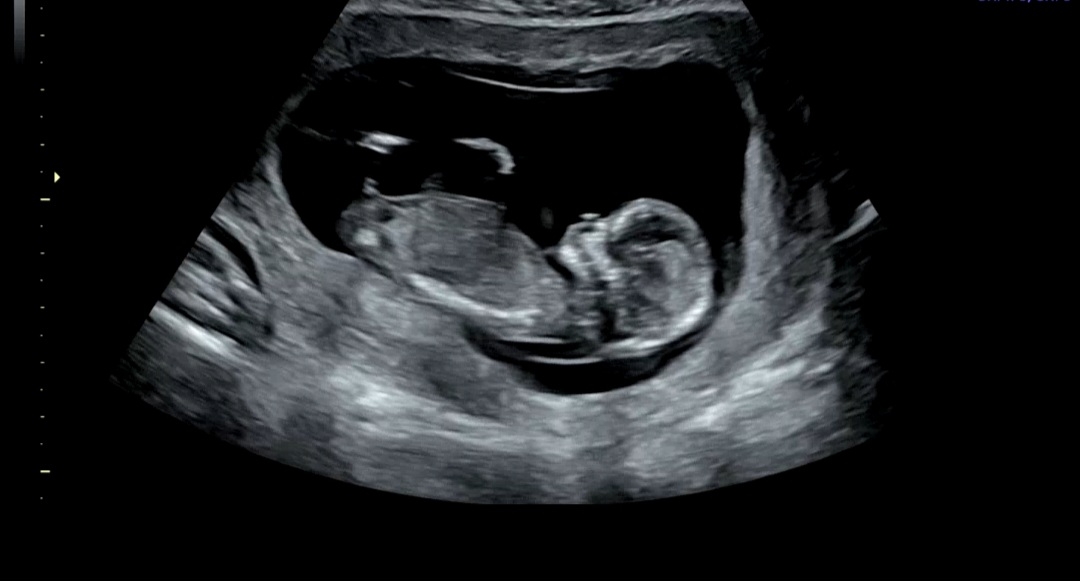

12주2일 초음파 보고왔는데용 성별 예측 가능할까요?!?! 성별 봐주세요!! 니프티검사도 하고왔어요 :)